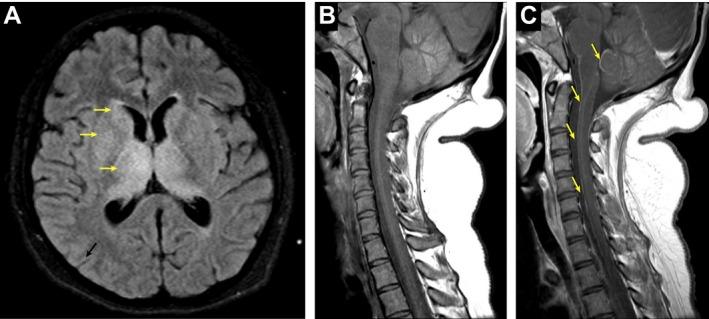

通过对一名肾移植患者脑脊液进行宏基因组深度测序诊断出急性西尼罗河病毒脑膜脑炎

Acute West Nile Virus Meningoencephalitis Diagnosed Via Metagenomic Deep Sequencing of Cerebrospinal Fluid in a Renal Transplant Patient.

Solid organ transplant patients are vulnerable to suffering neurologic complications from a wide array of viral infections and can be sentinels in the population who are first to get serious complications from emerging infections like the recent waves of arboviruses, including West Nile virus, Chikungunya virus, Zika virus, and Dengue virus. The diverse and rapidly changing landscape of possible causes of viral encephalitis poses great challenges for traditional candidate-based infectious disease diagnostics that already fail to identify a causative pathogen in approximately 50% of encephalitis cases. We present the case of a 14-year-old girl on immunosuppression for a renal transplant who presented with acute meningoencephalitis. Traditional diagnostics failed to identify an etiology. RNA extracted from her cerebrospinal fluid was subjected to unbiased metagenomic deep sequencing, enhanced with the use of a Cas9-based technique for host depletion. This analysis identified West Nile virus (WNV). Convalescent serum serologies subsequently confirmed WNV seroconversion. These results support a clear clinical role for metagenomic deep sequencing in the setting of suspected viral encephalitis, especially in the context of the high-risk transplant patient population.

摘要

实体器官移植患者容易因多种病毒感染而出现神经系统并发症,并且可能成为人群中的哨兵,率先从西尼罗河病毒、基孔肯雅病毒、寨卡病毒和登革热病毒等新发感染中出现严重并发症。病毒性脑炎的潜在病因多样且迅速变化,这给传统的基于候选病原体的传染病诊断带来了巨大挑战,在大约50%的脑炎病例中,传统诊断方法已无法确定致病病原体。我们报告了一例14岁接受肾移植免疫抑制治疗的女孩,她出现了急性脑膜脑炎。传统诊断未能确定病因。从她的脑脊液中提取的RNA进行了无偏倚的宏基因组深度测序,并使用基于Cas9的宿主耗竭技术进行了增强。该分析确定了西尼罗河病毒(WNV)。恢复期血清学检测随后证实了WNV血清转化。这些结果支持了宏基因组深度测序在疑似病毒性脑炎情况下的明确临床作用,特别是在高风险移植患者群体中。